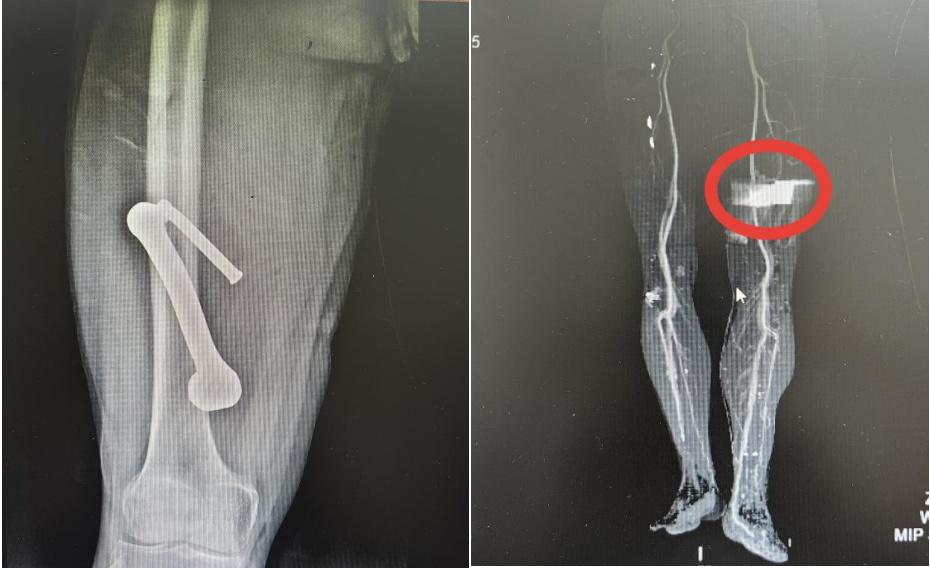

张先生被紧急送至医院急诊室时,三维血管造影检查显示,金属异物位置极为凶险:其穿行路径紧邻人体主要动脉之一的股动脉。异物与股动脉间距极小,一旦损伤该血管,将导致快速致命性大出血。

术中探查显示,那枚金属异物与股动脉、股静脉紧密相依,距离控制下肢运动与感觉的关键神经束——坐骨神经主干仅毫厘之遥。稍有偏差就可能引发致命性大出血,甚至导致患者永久性下肢瘫痪。

历经一个多小时的精细操作,徐楚江主任带领手术团队,将紧贴异物的股动静脉及其分支神经小心翼翼地分离并保护完好。在确认所有重要组织均得到妥善保护后,那根紧贴“生命线”的致命金属异物被完整平稳取出!